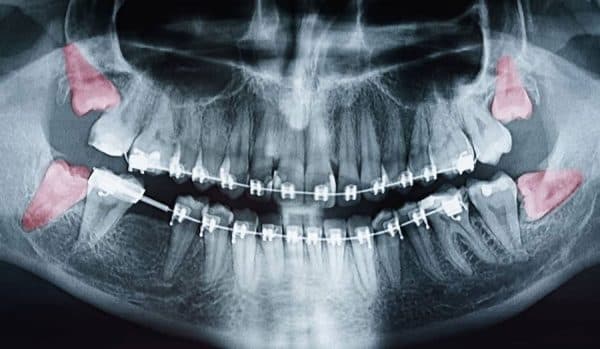

Răng khôn mọc lệch nguy hiểm khó lường

Răng khôn là răng mọc trong độ tuổi trưởng thành lúc này xương hàm đã ngừng tăng trưởng và phát triển, xương trở nên cứng đặc hơn. Bên cạnh đó, ngày nay xương hàm cũng giảm sự phát triển do chế độ ăn mềm. Đây chính là những nguyên nhân gây nên sự mất cân bằng giữa răng và kích thước xương hàm, dẫn đến tình trạng răng khôn mọc lệch hay mọc ngầm làm ảnh hưởng đến sức khỏe và khả năng ăn nhai.

Răng khôn mọc lệch hoặc mọc ngầm có thể gây ra nhiều vấn đề nguy hiểm. Trường hợp răng khôn kẹt trong xương hàm hoặc nướu răng, trong quá trình mọc răng sẽ gây áp lực lên vùng xương và nướu, cùng với việc thức ăn đọng bên dưới nướu phủ trên răng khôn không thể làm sạch được dẫn đến viêm nhiễm.

Răng khôn mọc lệch, không chỉ dễ gây mắc thức ăn tạo điều kiện cho vi khuẩn phát triển mà còn có thể tác động lên răng bên cạnh gây xô lệch hàm, áp lực mọc răng khôn cũng có thể gây ra tiêu ngót chân răng của răng bên cạnh. Bên cạnh đó, răng khôn có thể thoái hóa thành u, nang bệnh lý trong xương hàm, làm yếu xương hàm.